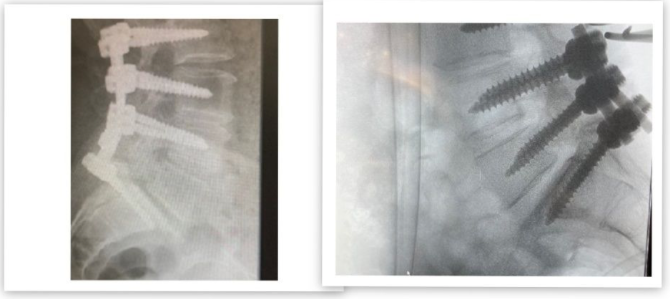

Paciente con IMC> 35% que ingresó por: ciática izquierda que no mejoró con tratamiento médico, presentó afectación vesical. Se decidió realizar la discectomía mediante la técnica MIS: tras la cirugía, la paciente mejoró su proceso doloroso y al día siguiente se retiró la sonda vesical. Es dada de alta a los dos días de ingreso en el Hospital.